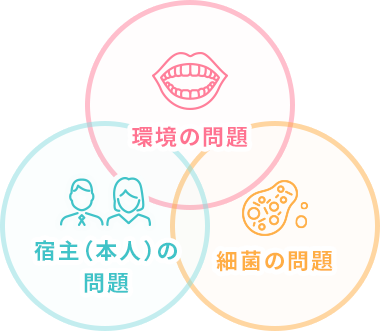

歯周病(歯槽膿漏)が発生するメカニズムは3つに分類することができます。

これら3つが重なった時に、初めて歯周病(歯槽膿漏)を発症します。

逆に、これらの関係を引き離すことができれば、歯周病(歯槽膿漏)を予防できるという事になるのです。

01環境の問題

お手入れの不足、唾液量の低下、喫煙、服薬

02宿主(本人)の問題

ストレス、噛み合わせ、歯並び、習癖(ずっと噛み合わせている等)人種(アジア人は、人種的に歯周病になりやすい)、メカニカルストレス、浸出液中の物質

03細菌の問題

プラーク(バイオフィルム)の病原性の強弱、種類